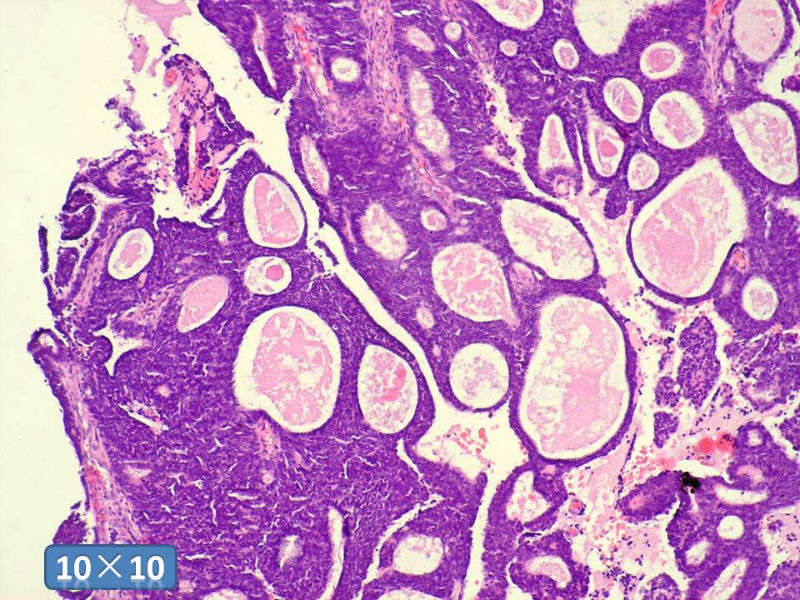

男性,49岁,间断左鼻腔出血3个月。

标签:是嗅母么?

1)嗅神经母细胞瘤?

2)腺肌上皮癌?

3)肌上皮癌?

4)神经内分泌癌?

5)腺样囊性癌?

6)其他?

腺肌上皮癌

感觉要排除畸胎癌肉瘤。

间质为恶性梭形细胞成分,其间感觉是腺体,两种成分密切相关....

免疫组化S-100的阳性区域方式...嗅母可能性大。

支持嗅神经母细胞瘤(伴有腺体分化)

嗅神经母细胞瘤

有上皮和间叶2种结构,畸胎性癌肉瘤是要考虑一下的吧!